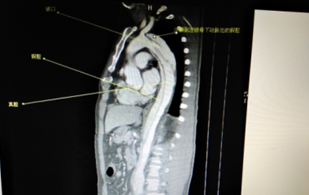

術(shù)前CT檢查(顯示為主動脈夾層)

術(shù)中(釋放支架)